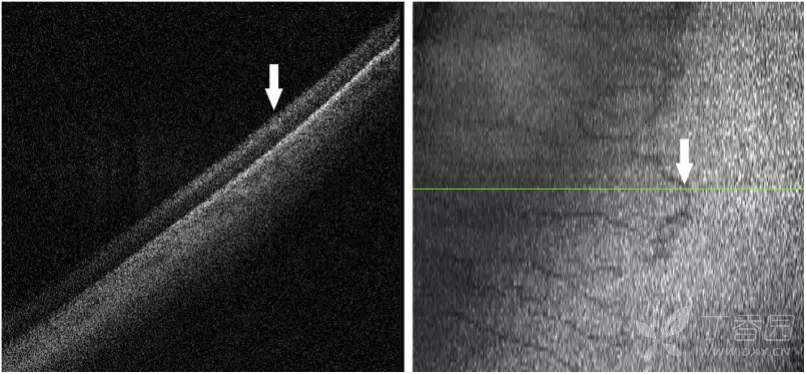

ROP 1至3期OCT图像

图. OCT图像上的1期分界线(白箭)与视网膜血管-无血管连接处对齐。

图. OCT图像上的2期脊(白箭)表现为视网膜内层局灶性增厚、隆起,与en face图像上血管区-无血管区交界处较宽的暗边界一致。

图. OCT图像和en-face图像显示3期视网膜外新生血管形成(白箭)。